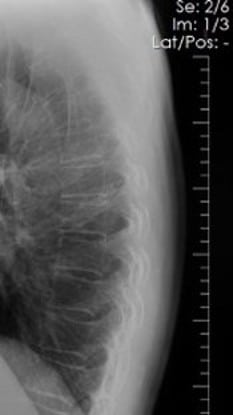

This 67-year old female patient presented to the ER with shortness of breath, in conjunction with chronic pain in her posterior thoracic region upon taking a large breath in. The reading radiologist noticed a suspicious mass-like opacity in the Lateral view. The radiologist stated that, thanks to the DE images, they could they tell the opacity wasn’t a lung mass, but instead far less concerning bony outcroppings from the thoracic vertebrae.